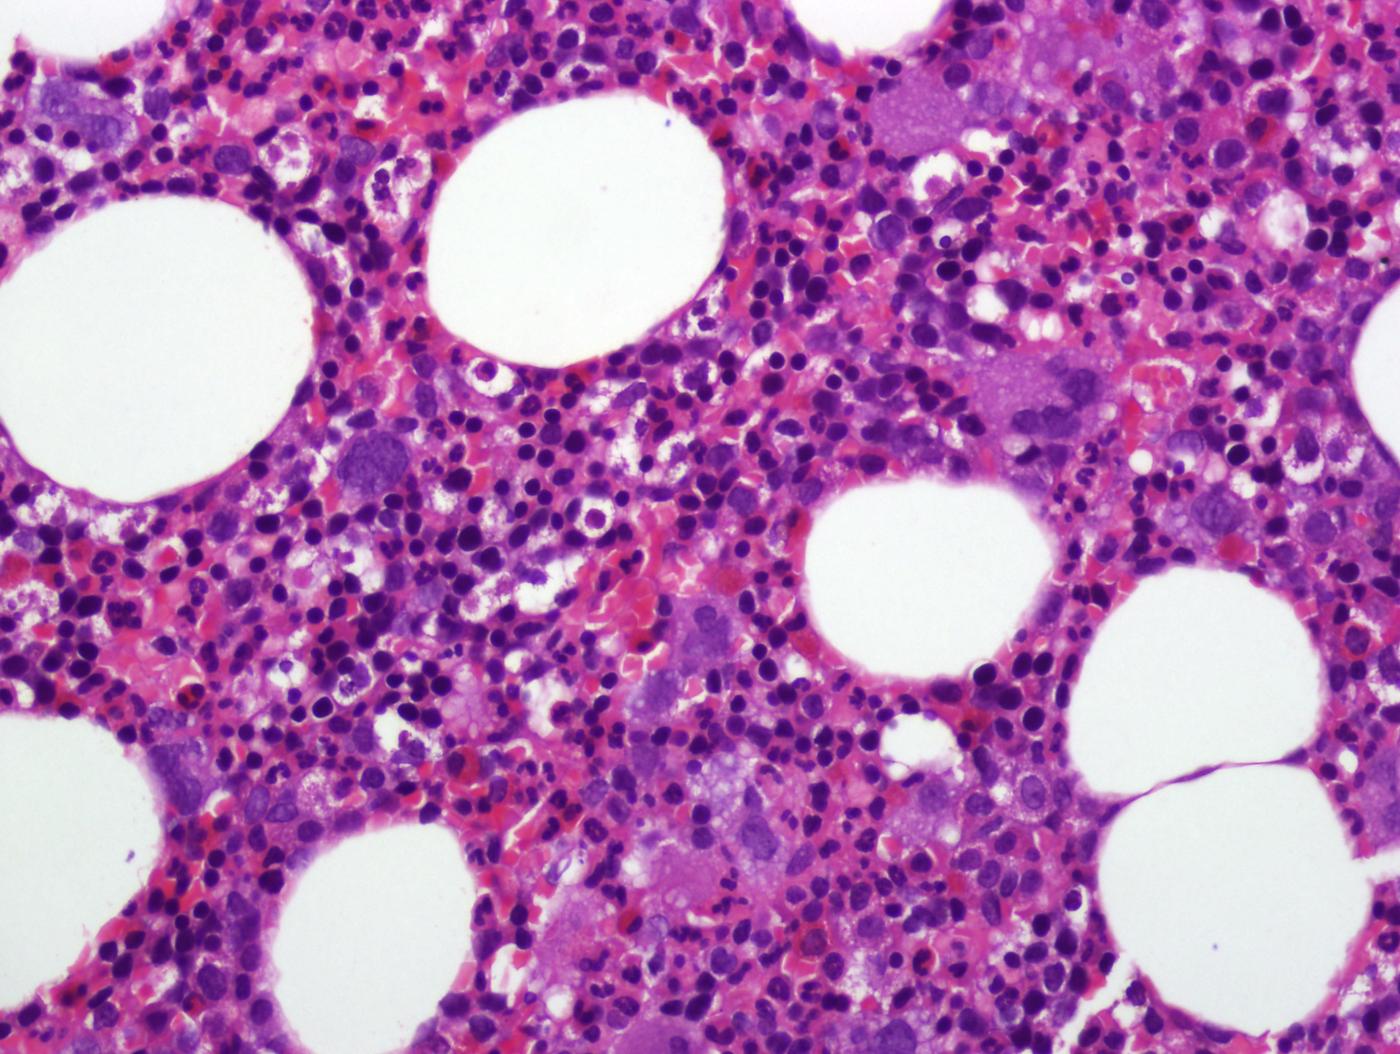

Es fa principalment mitjançant una analítica en què s'evidencien valors alts d'hemoglobina i hematòcrit, també poden augmentar les plaquetes i els glòbuls blancs. A més, també es du a terme un estudi molecular (mutació del gen JAK2) mitjançant analítica. De vegades poden ser necessaris altres estudis per completar el diagnòstic, com per exemple una biòpsia de medul·la òssia.